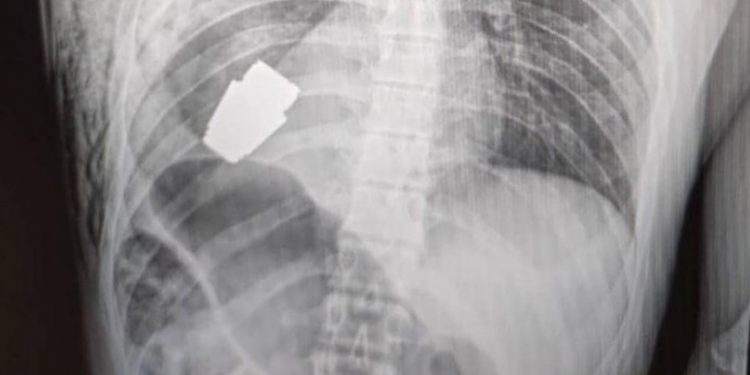

Un soldado ucraniano se sometió a una peligrosa operación en donde le extrajeron una granada sin estallar desde el interior de su pecho. Los cirujanos sacaron el arma explosiva justo por debajo del corazón.

Anton Gerashchenko, asesor ministerial de Asuntos Internos de Ucrania, mencionó que un equipo militar neutralizó la munición para que esta no explotará. Además, catalogo el procedimiento como uno que «se incluiría en los libros de texto de medicina», según publicó The Guardian.

«Tras tratarse de una operación con armas explosivas, se llevó a cabo sin usar electrocoagulación, es decir, sin uno de los métodos fundamentales para controlar el sangrado durante una cirugía. La granada podría detonar en cualquier momento”, dijo Hanna Maliar, viceministra de defensa de Ucrania.